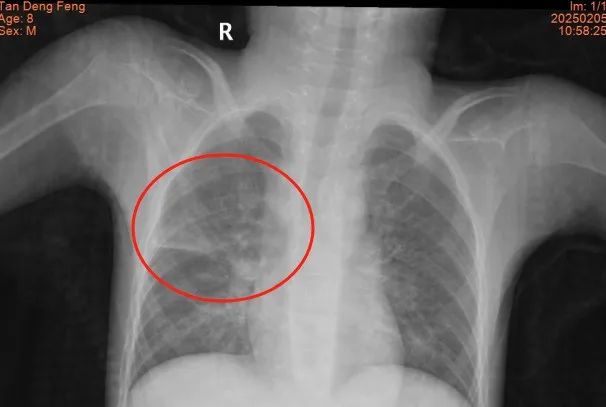

接診后,我院兒科團(tuán)隊(duì)第一時(shí)間組織呼吸與危重癥醫(yī)學(xué)科、藥學(xué)部等多學(xué)科專(zhuān)家會(huì)診,全面評(píng)估患兒病情后,制定了以抗感染、控制驚厥發(fā)作為核心,輔以營(yíng)養(yǎng)支持和康復(fù)治療的個(gè)性化治療方案。治療過(guò)程中,團(tuán)隊(duì)查閱了大量國(guó)內(nèi)外文獻(xiàn),結(jié)合患兒的具體情況,創(chuàng)新性地采用了一系列治療手段,包括輔助排痰和肺部物理治療等,逐步改善了患兒的癥狀。經(jīng)過(guò)40余天的全力救治,患兒的感染得到有效控制,體溫恢復(fù)正常,呼吸功能顯著改善,肺部感染及膿腫完全吸收,最終順利出院。出院當(dāng)天,患兒家屬激動(dòng)地表示:“是醫(yī)護(hù)人員的堅(jiān)持和專(zhuān)業(yè)治療給了孩子第二次生命!”